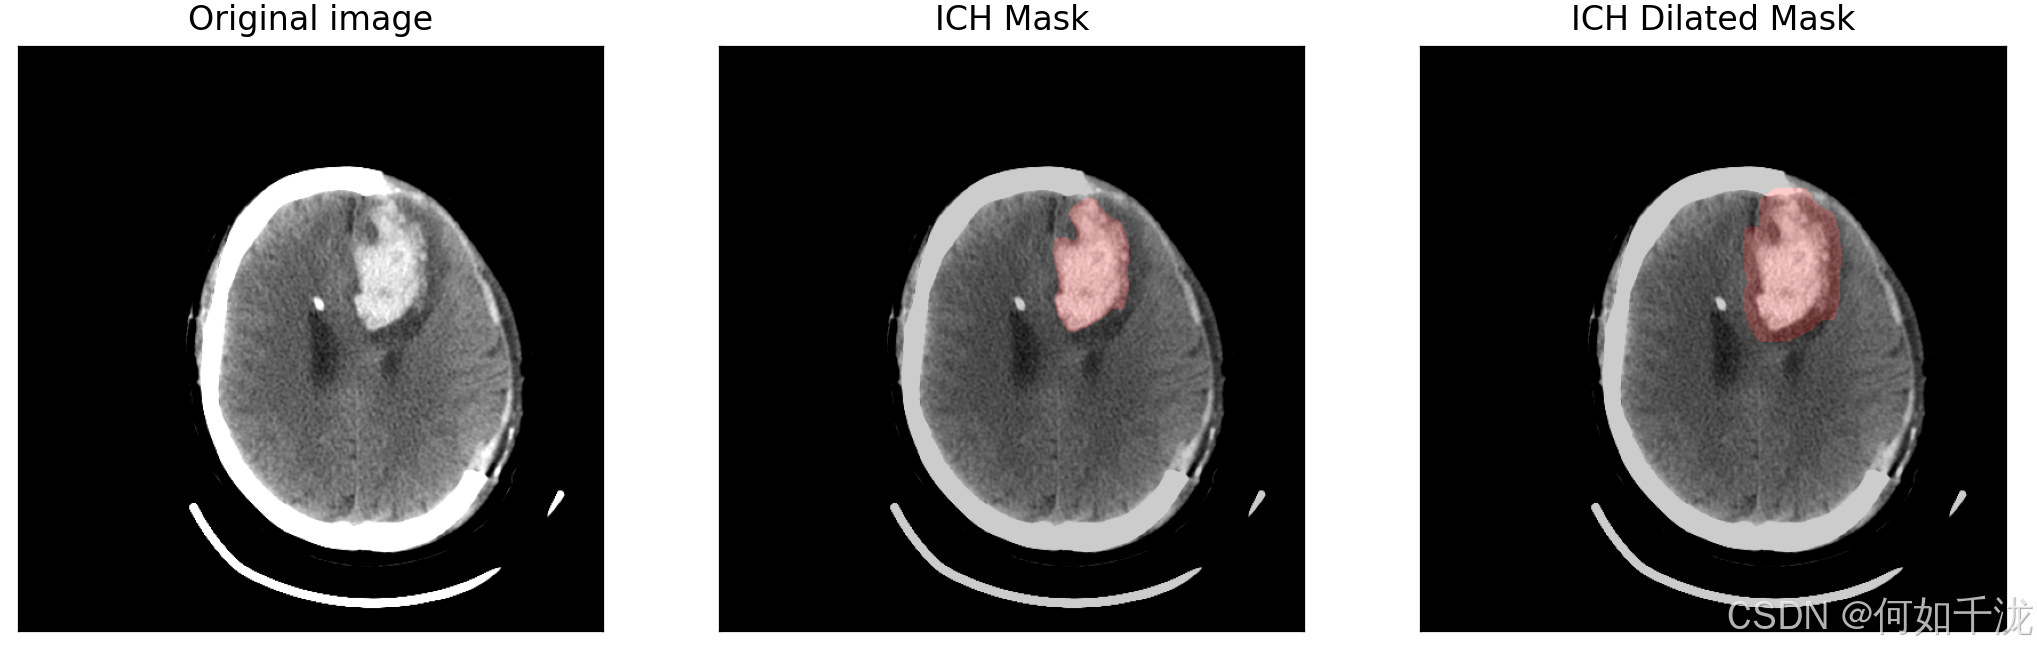

plt.subplot(1, 3, 1)

plt.title("Original image")

plt.imshow(img, cmap='gray')

plt.title("ICH Mask")

plt.subplot(1, 3, 3)

plt.title(f"ICH Dilated Mask")

ich_dilated = dilation(ich, square(dilation_size))